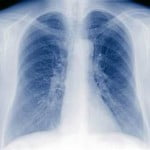

BOLOGNA, 30 MAR – Un passaporto sanitario per censire lo stato di salute degli immigrati. A chiederlo e’ la Lega Nord di Bologna, citando i ”preoccupanti” numeri della diffusione della tubercolosi in citta’.

La richiesta, avanzata in una Commissione consiliare attraverso anche la presentazione di un ordine del giorno ad hoc, e’ stata respinta con forza dal Pd. Ma Franco Falcone, direttore dell’unita’ operativa di malattie dell’apparato respiratorio dell’ospedale Bellaria, ha riconosciuto l’utilita’ di uno studio della situazione. (ANSA).